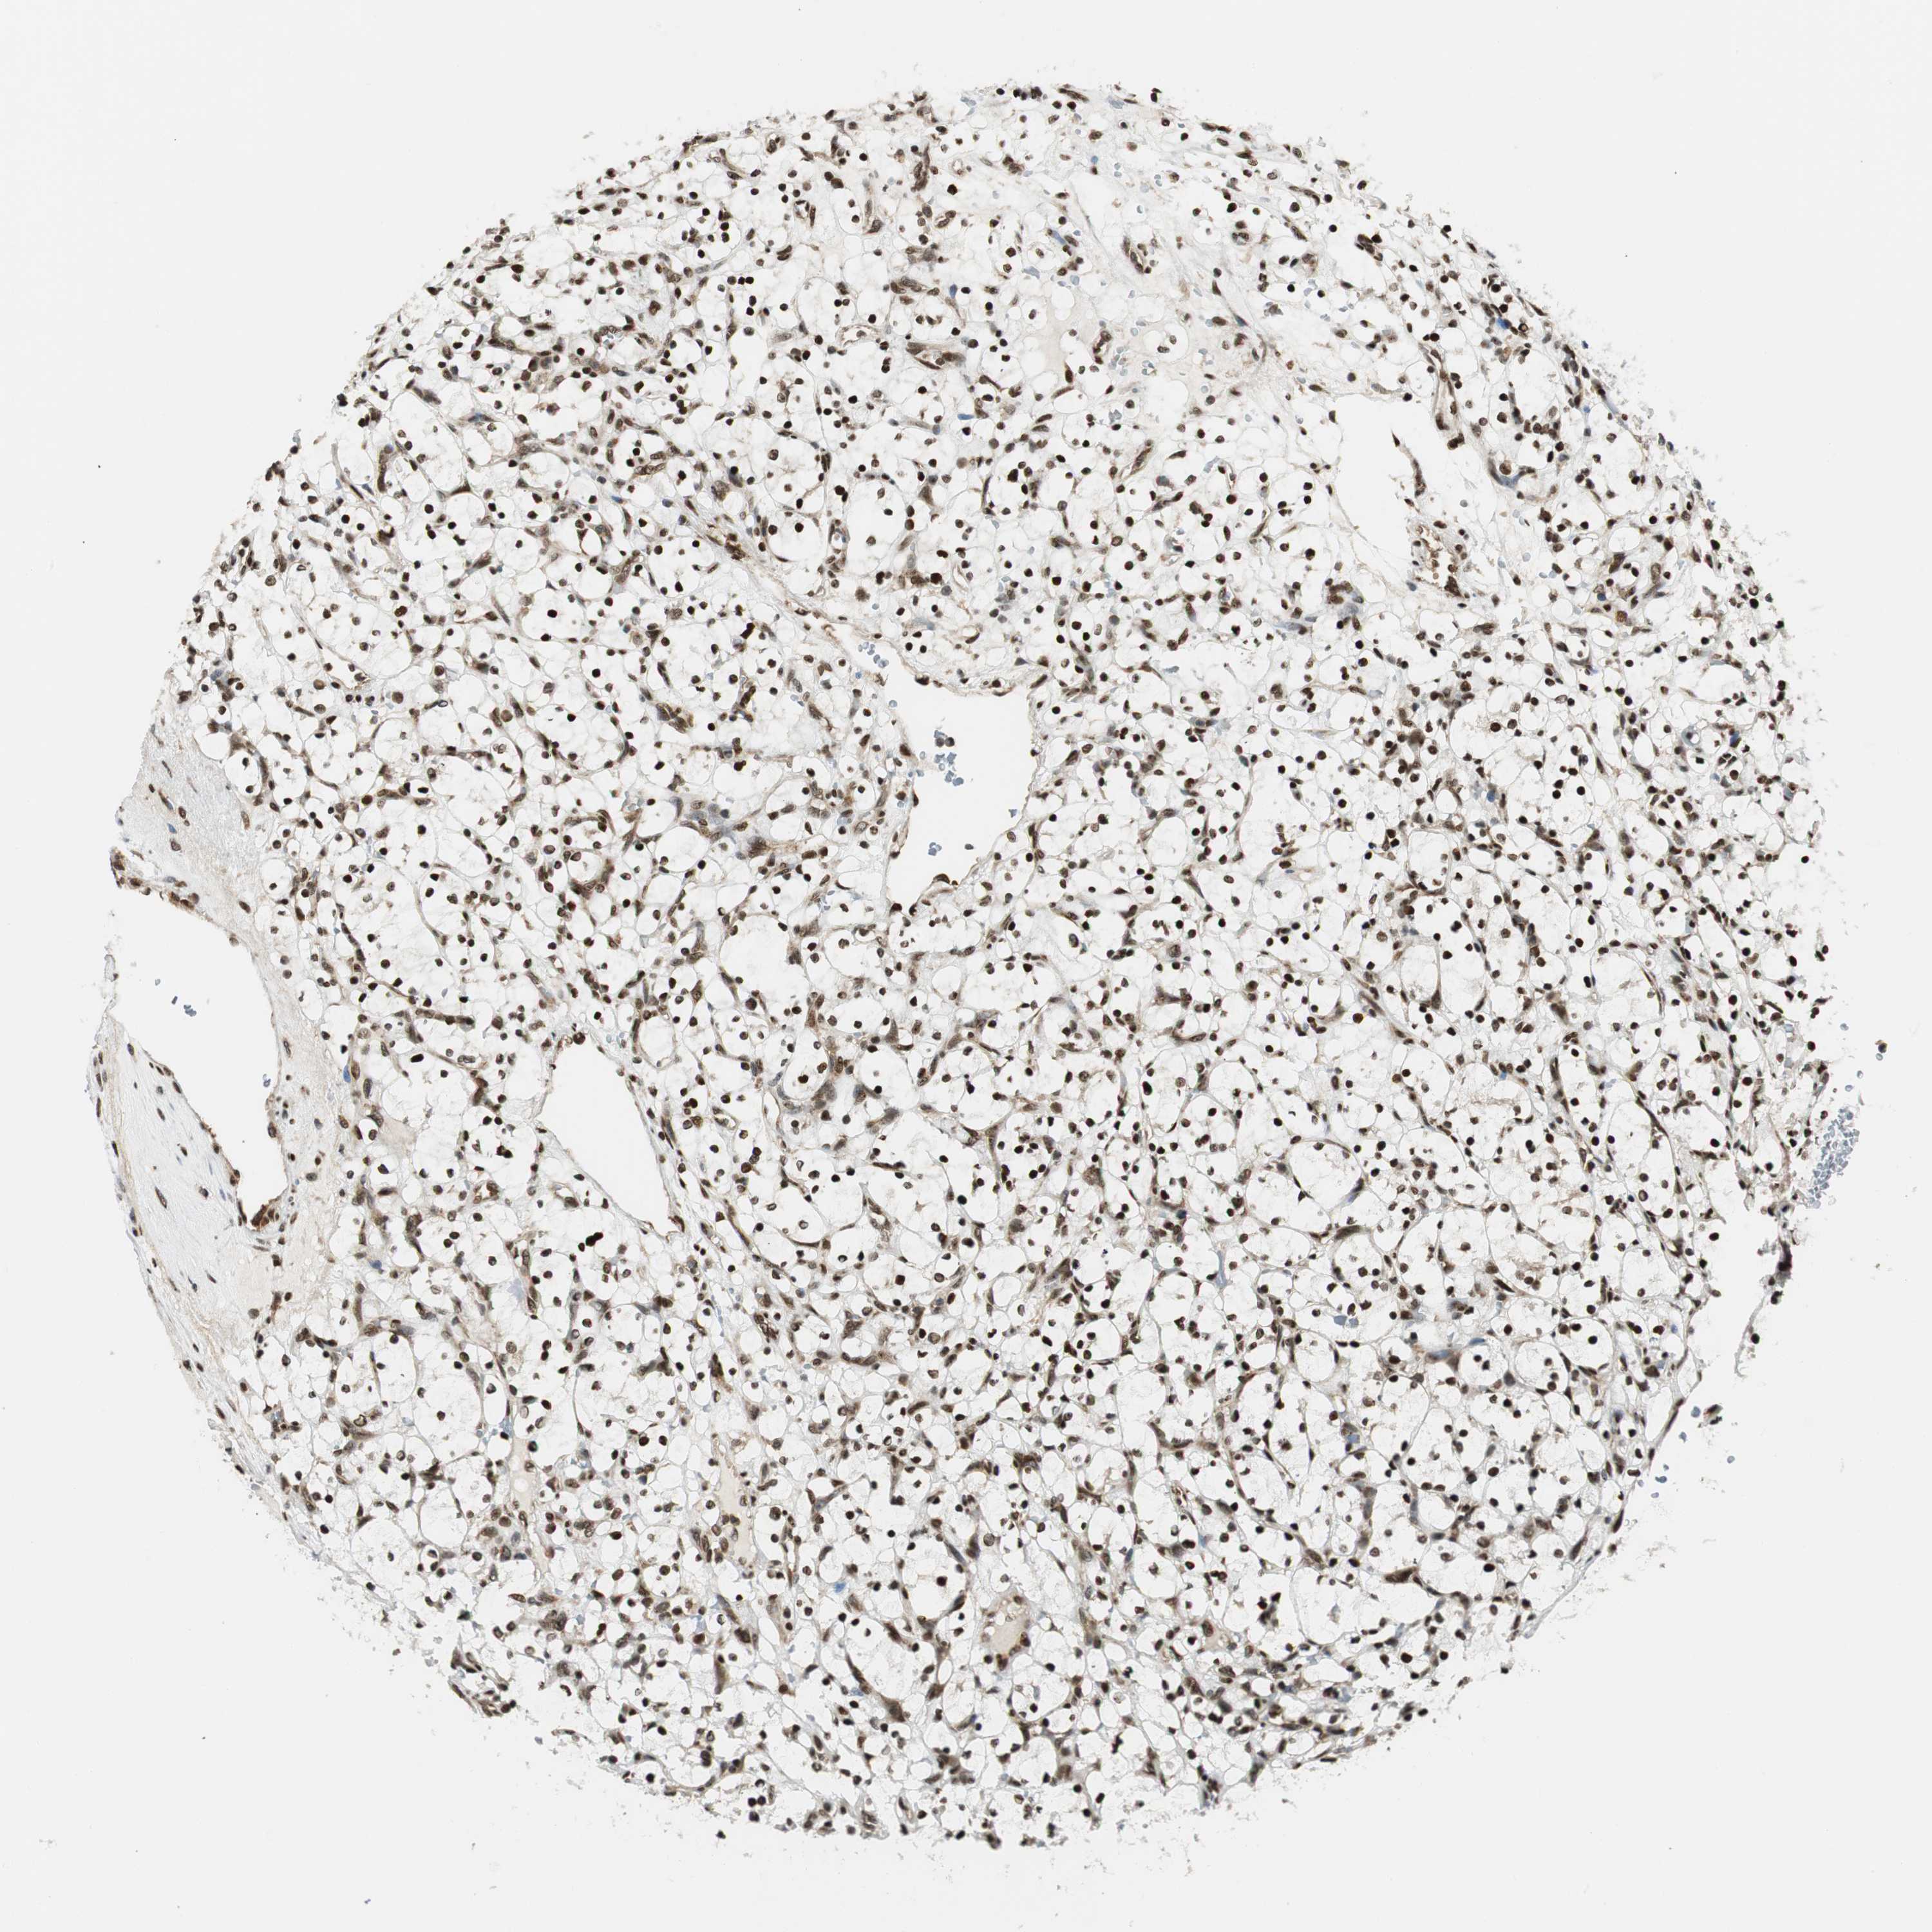

KIDNEY RENAL CLEAR CELL CARCINOMA (TCGA) - Interactive survival scatter ploti

The Survival Scatter plot shows the clinical status (i.e. dead or alive) for all individuals in the patient cohort, based on the same data that underlies the corresponding Kaplan-Meier plots. Patients that are alive at last time for follow-up are shown in blue and patients who have died during the study are shown in red.

The x-axis shows the expression levels (FPKM) of the investigated gene in the tumor tissue at the time of diagnosis. The y-axis shows the follow-up time after diagnosis (years). Both axes are complimented with kernel density curves demonstrating the data density over the axes. The top density plot shows the expression levels (FPKM) distribution among dead (red) and alive patients (blue). The right density plot shows the data density of the survived years of dead patients with high and low expression levels respectively, stratified using the cutoff indicated by the vertical dashed line through the Survival Scatter plot. This cutoff is automatically defined based on the FPKM cutoff that minimizes the p-score. The cutoff can be changed by dragging the vertical line or by entering a cutoff value in the square labeled "Current cut-off".

Under the Survival Scatter plot the p-score landscape (black curve; left axis) is shown together with dead median separation (red curve; right axis). Dead median separation is the difference in median mRNA expression between patients who have died with high and low expression, respectively. It is calculated as follows: median FPKM expression of dead patients with high expression - median FPKM expression of dead patients with low expression. This is intended to aid the user in visually exploring custom cutoffs and the associated p-scores and dead median separation.

Individual patient data is displayed and can be filtered by clicking on one or more of the category buttons on the top of the page. Categories describing expression level and patient information include: high, low, alive, dead, female, male and tumor stages. The scale of the x-axis can be toggled between linear and log-scale by clicking on the "x log" button. Mouse-over function shows TCGA ID, patient information and mRNA expression (FPKM) for each patient.

& Survival analysisi

Kaplan-Meier plots summarize results from analysis of correlation between mRNA expression level and patient survival. Patients were divided based on level of expression into one of the two groups "low" (under cut off) or "high" (over cut off). X-axis shows time for survival (years) and y-axis shows the probability of survival, where 1.0 corresponds to 100 percent.

RING1 is not prognostic in Kidney Renal Clear Cell Carcinoma (TCGA)

: 22.11

Average pTPM 27.4

Number of samples 521